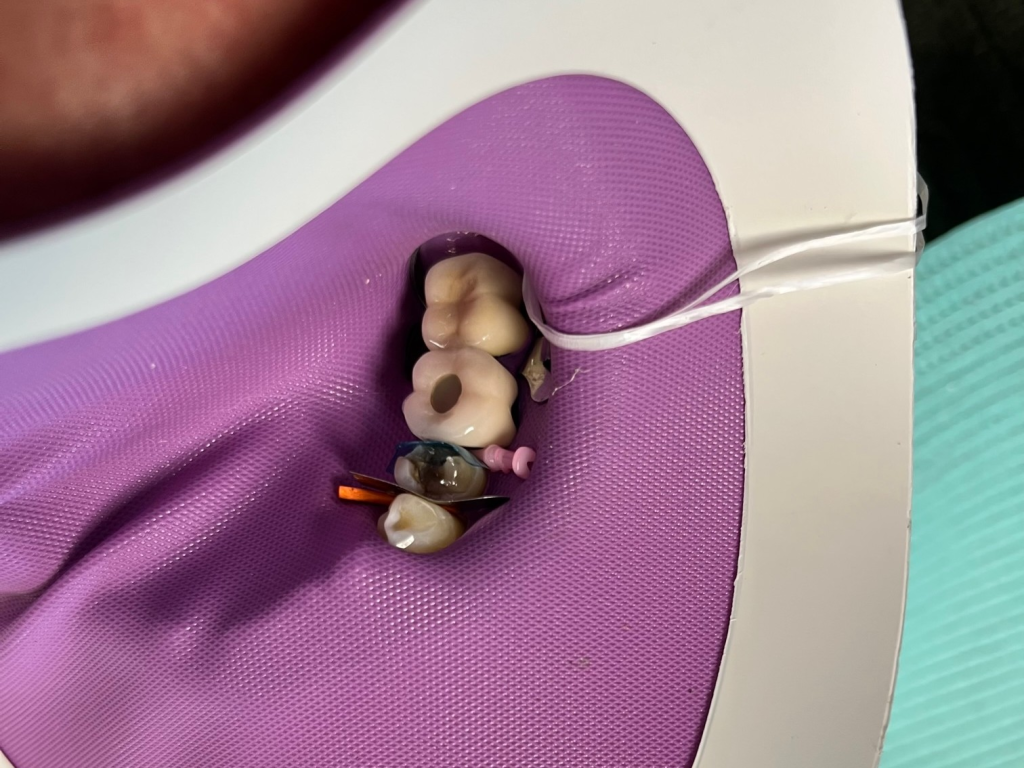

Posterior DentXpinTM repair.